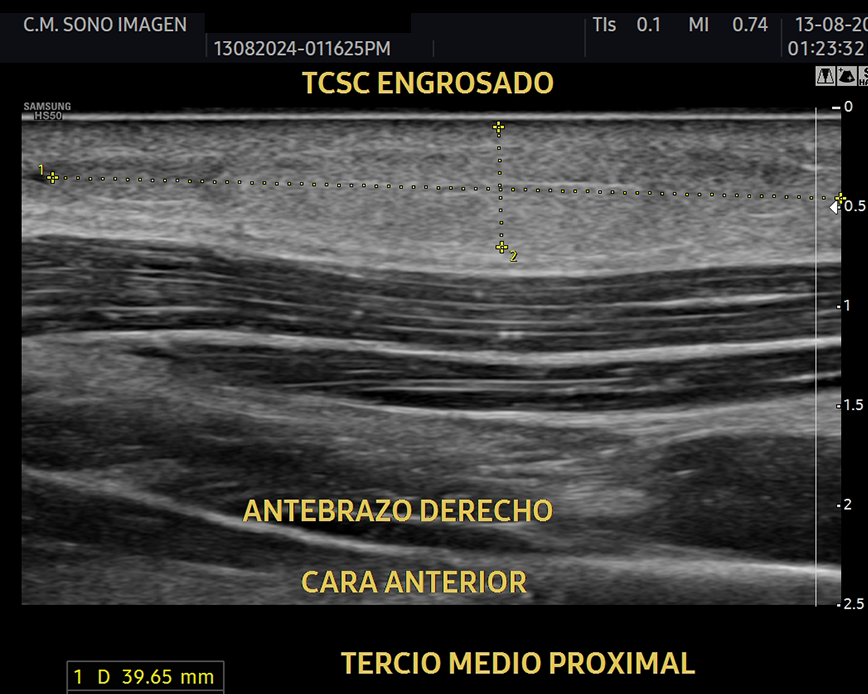

Es un procedimiento no invasivo y seguro , incluido niños, ya que no usamos radiación ionizante. Permite realizar un diagnóstico en tiempo real y podemos evaluar tendones, músculos, ligamentos, articulaciones y nervios.

Ecografía de rodilla

- evaluación del dolor de rodilla

- lesiones de tejidos blandos: tendinosis, desgarros ligamentosos, rupturas meniscales.